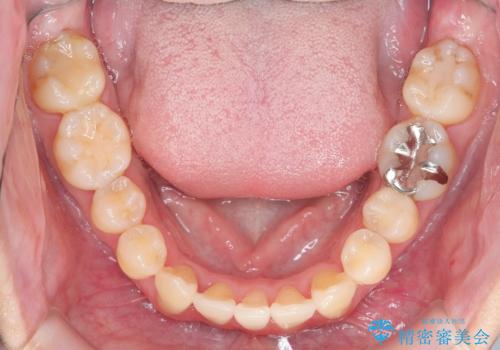

ねじれ・がたつきのある前歯を改善

- がたつき・すれ違い、ねじれのある前歯の見た目、噛み合わせの改善を希望され来院されました。

4本の小臼歯抜歯を避け、下顎前歯の1本抜歯の極力少ない抜歯本数で審美的な歯並びを得る治療計画としました。

すれ違いを治すのが得意な前歯部の部分ワイヤーを用いることで、治療期間を短縮することができました。

見た目の改善だけでなく、噛みやすくなったことにも満足いただくことができました。